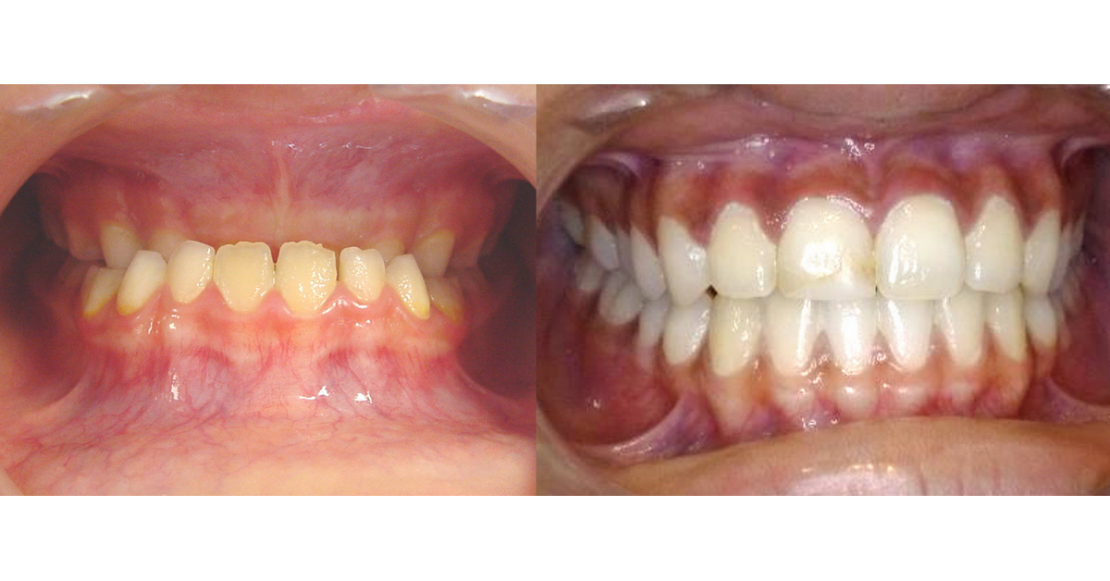

L'intérêt de ce cas clinique réside dans la durée du suivi post traitement : plus de 10 ans. Une prise en charge précoce (avant l'éruption des deuxième molaires) avec une correction tridimensionnelle : disjonction, réorientation du plan d'occlusion et avancée maxillaire permet d'obtenir une cinématique mandibulaire vertueuse pour la suite de la croissance, et donc une classe I ... stable dans le temps !